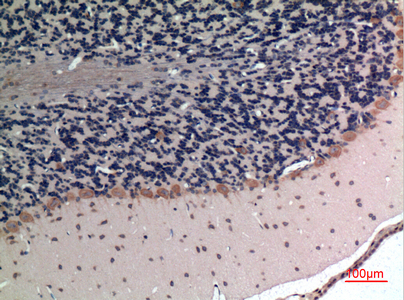

Immunohistochemical analysis of paraffin-embedded rat-brain, antibody was diluted at 1:100